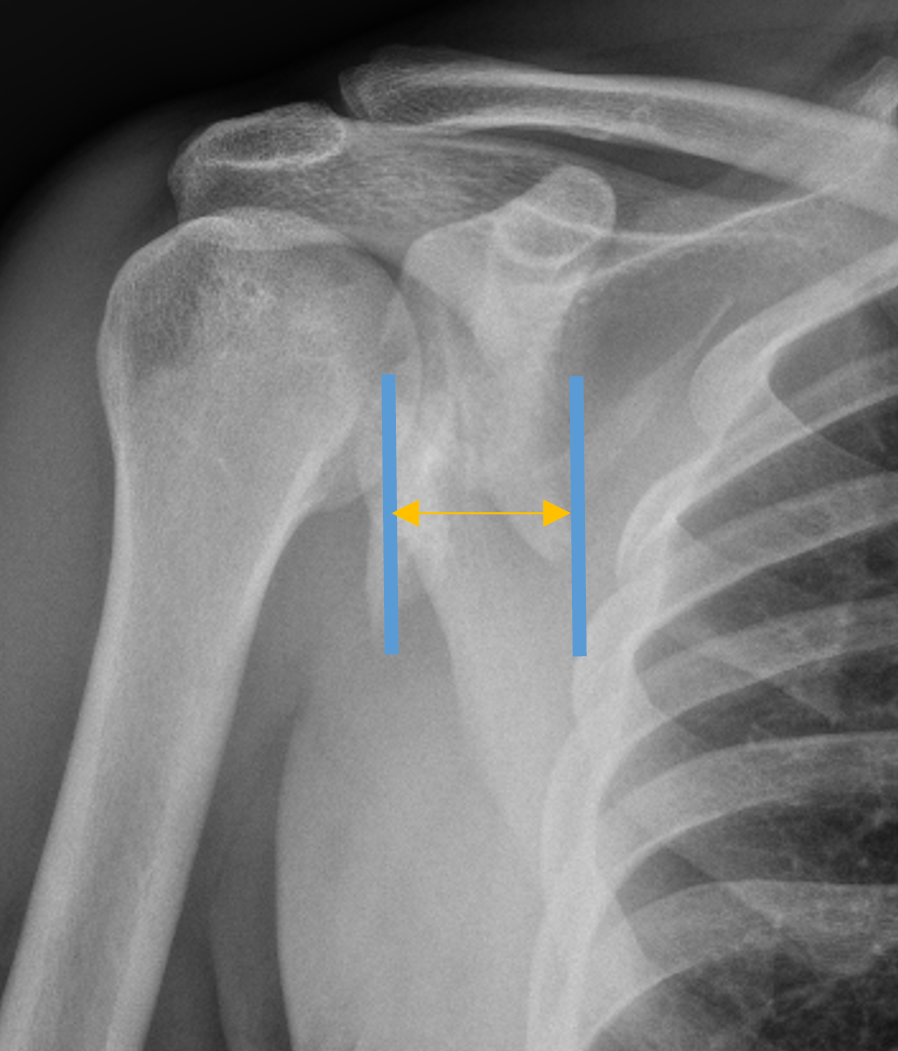

| Glenoid neck displacement | Glenoid neck angulation | Glenopolar angle |

|---|---|---|

| > 2cm medial displacement | > 45° angular deformity | < 22° glenopolar angle |

Medial displacement